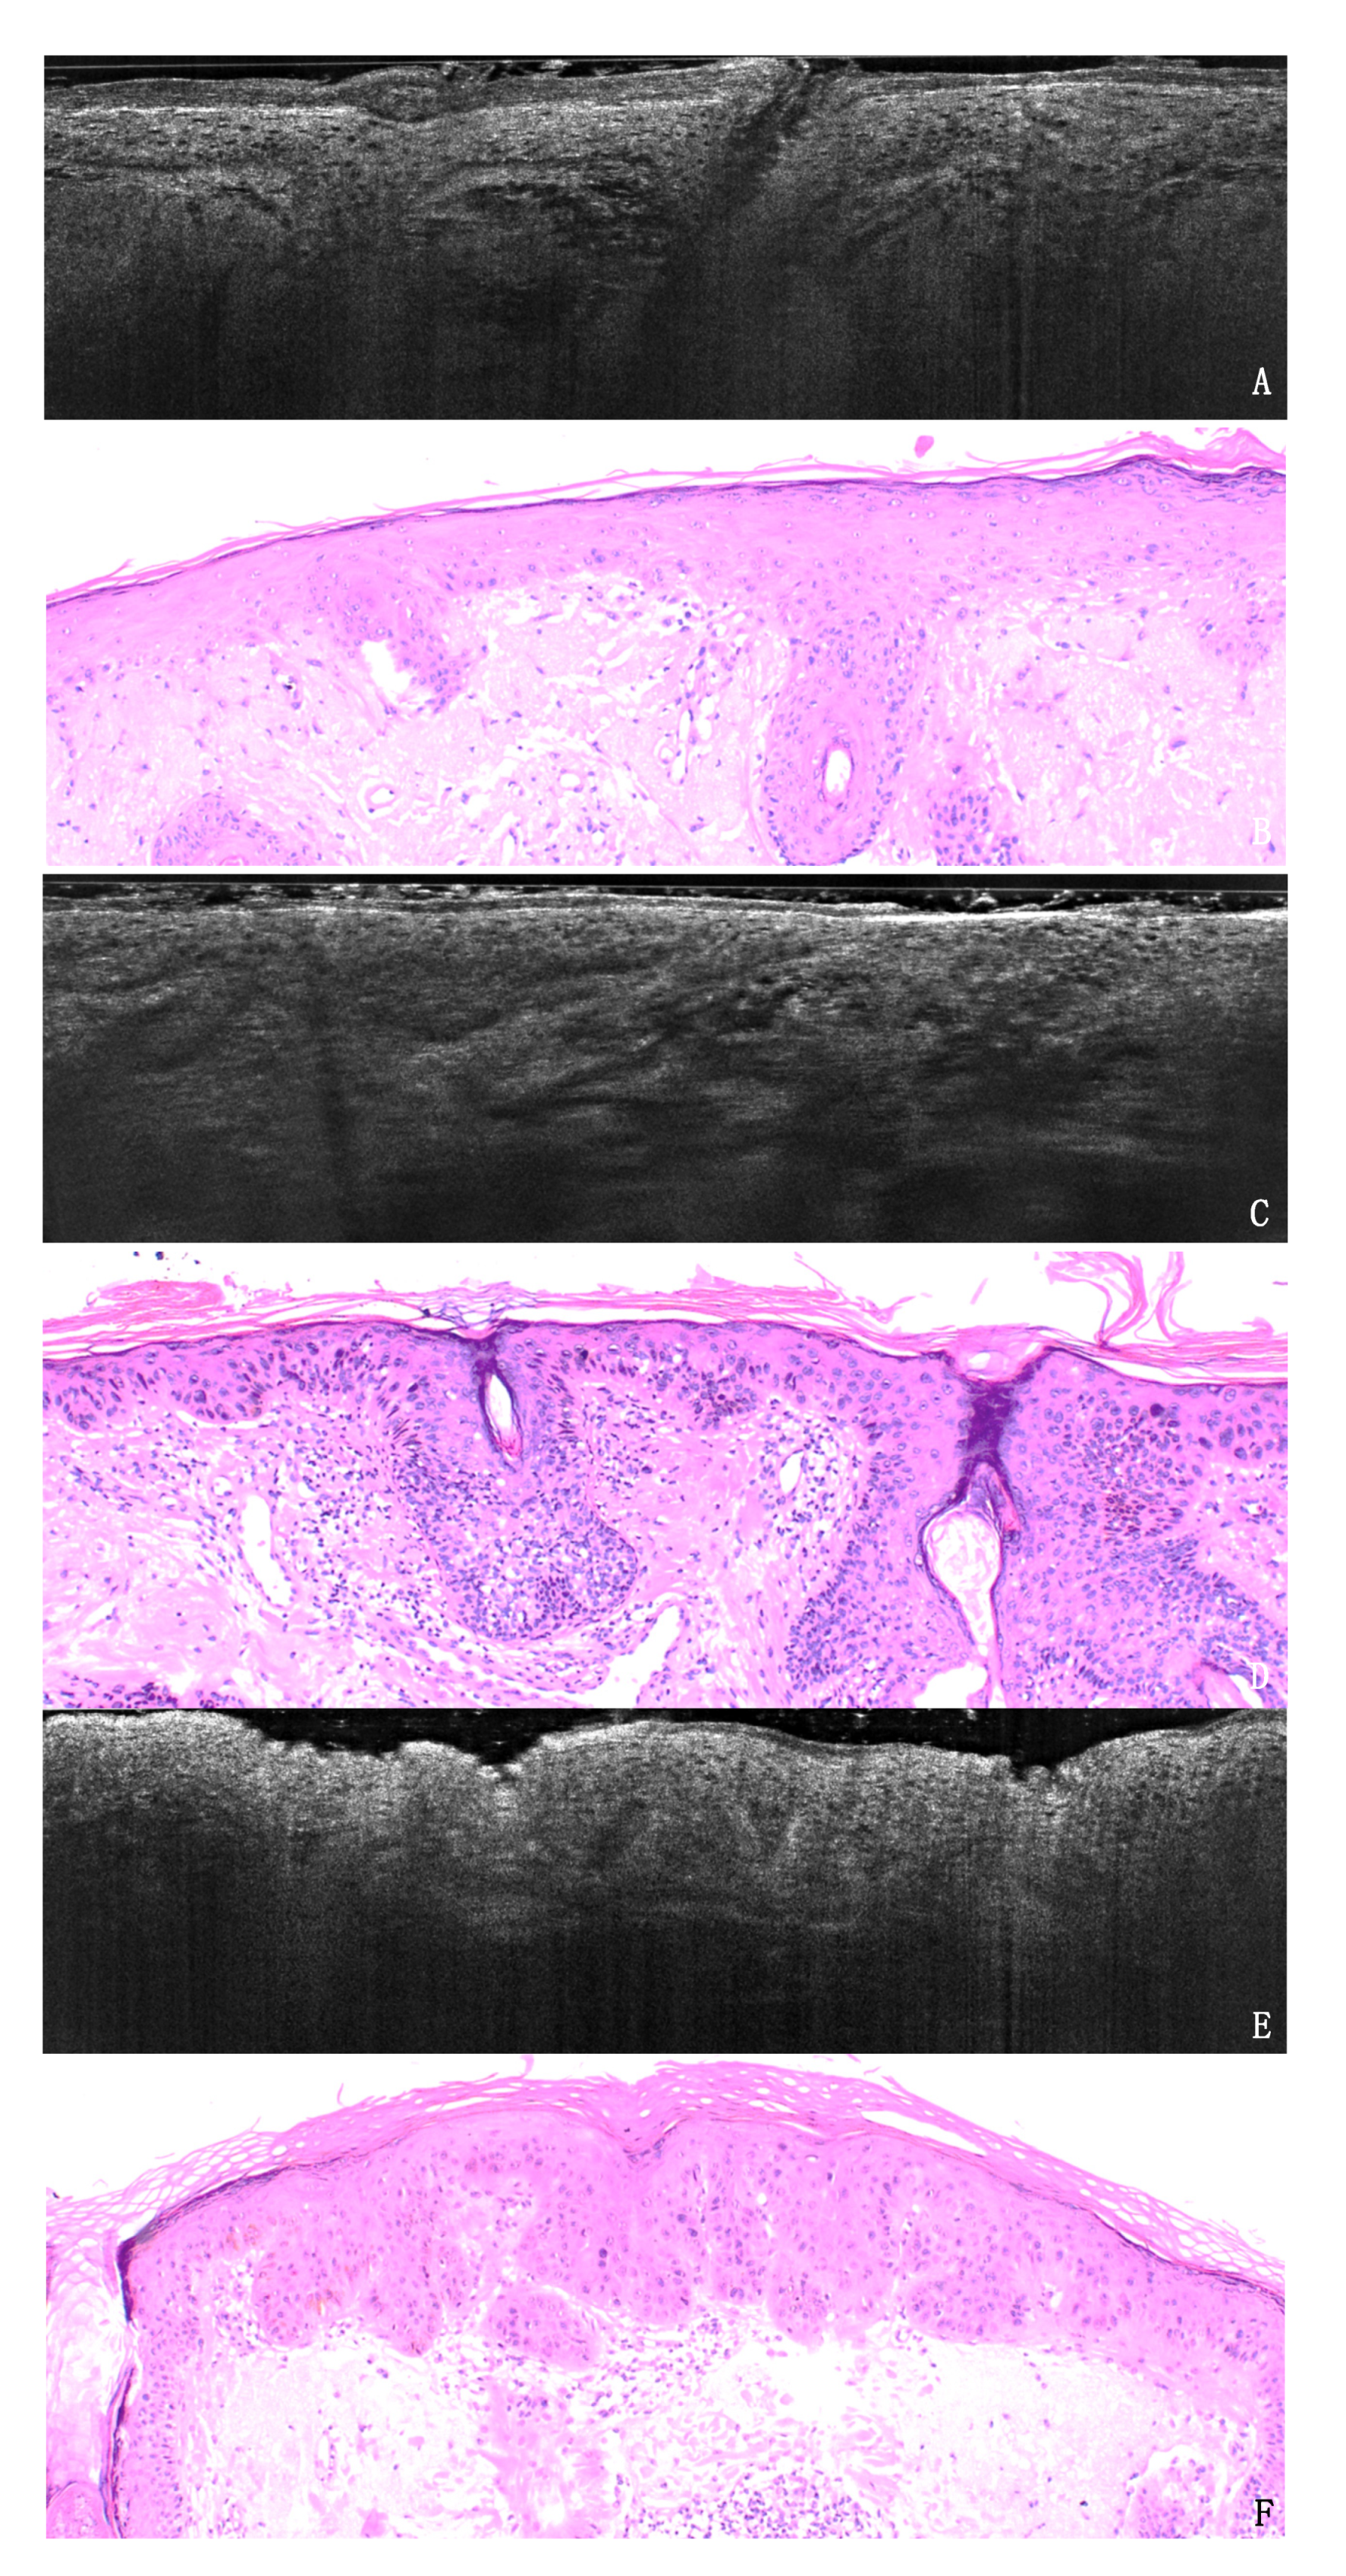

In-Vivo LC-OCT Evaluation of the Downward Proliferation Pattern of Keratinocytes in Actinic Keratosis in Comparison with Histology: First Impressions from a Pilot Study

3. Results

3.1. PRO Grading